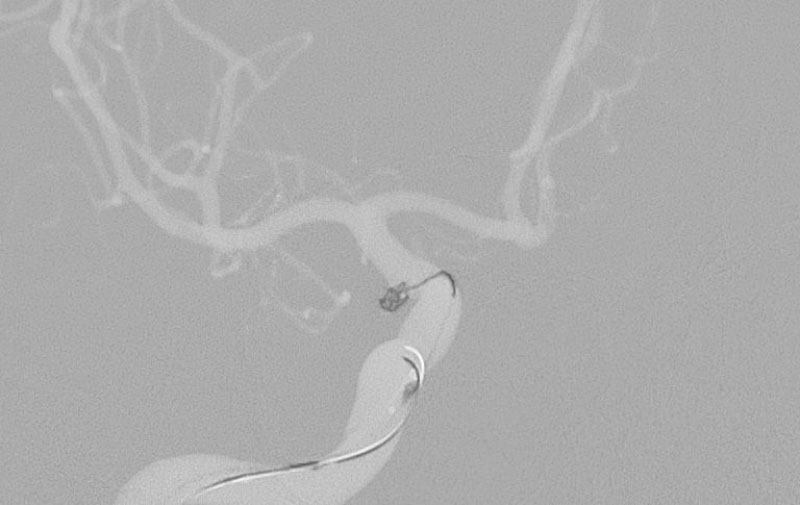

'25年10月

くも膜下出血

前交通動脈瘤破裂

40代

大阪府の病院

No.1589 手術前

No.1589 手術中

No.1589 手術後